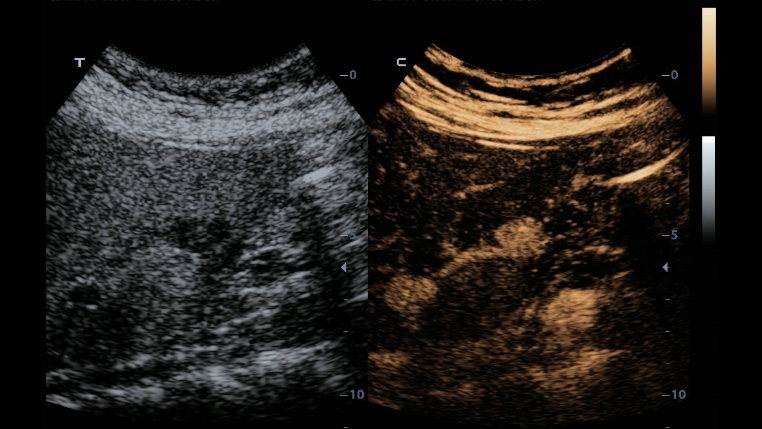

TecnologĂas de imagen clĂĄsicas: aumenta la calidad del diagnĂłstico

Mediante la aplicaciĂłn de tecnologĂas de imagen clĂĄsicas, que se migran desde los sistemas de ultrasonido establecidos, DC-40 con Full HD le proporciona una calidad de la imagen mĂĄs detallada y nĂtida.

- iClear (TecnologĂa de imagen con reducciĂłn de moteado)

- PSH (ImĂĄgenes por armĂłnicos con desplazamiento de fase)

- iBeam: tecnologĂa de formaciĂłn de imĂĄgenes espaciales compuestas

Gracias a una combinaciĂłn versĂĄtil de transductores, DC-40 con Full HD ofrece el mejor rendimiento equilibrado en una amplia gama de aplicaciones y produce una calidad de imagen avanzada para una gran variedad de tipos de pacientes.